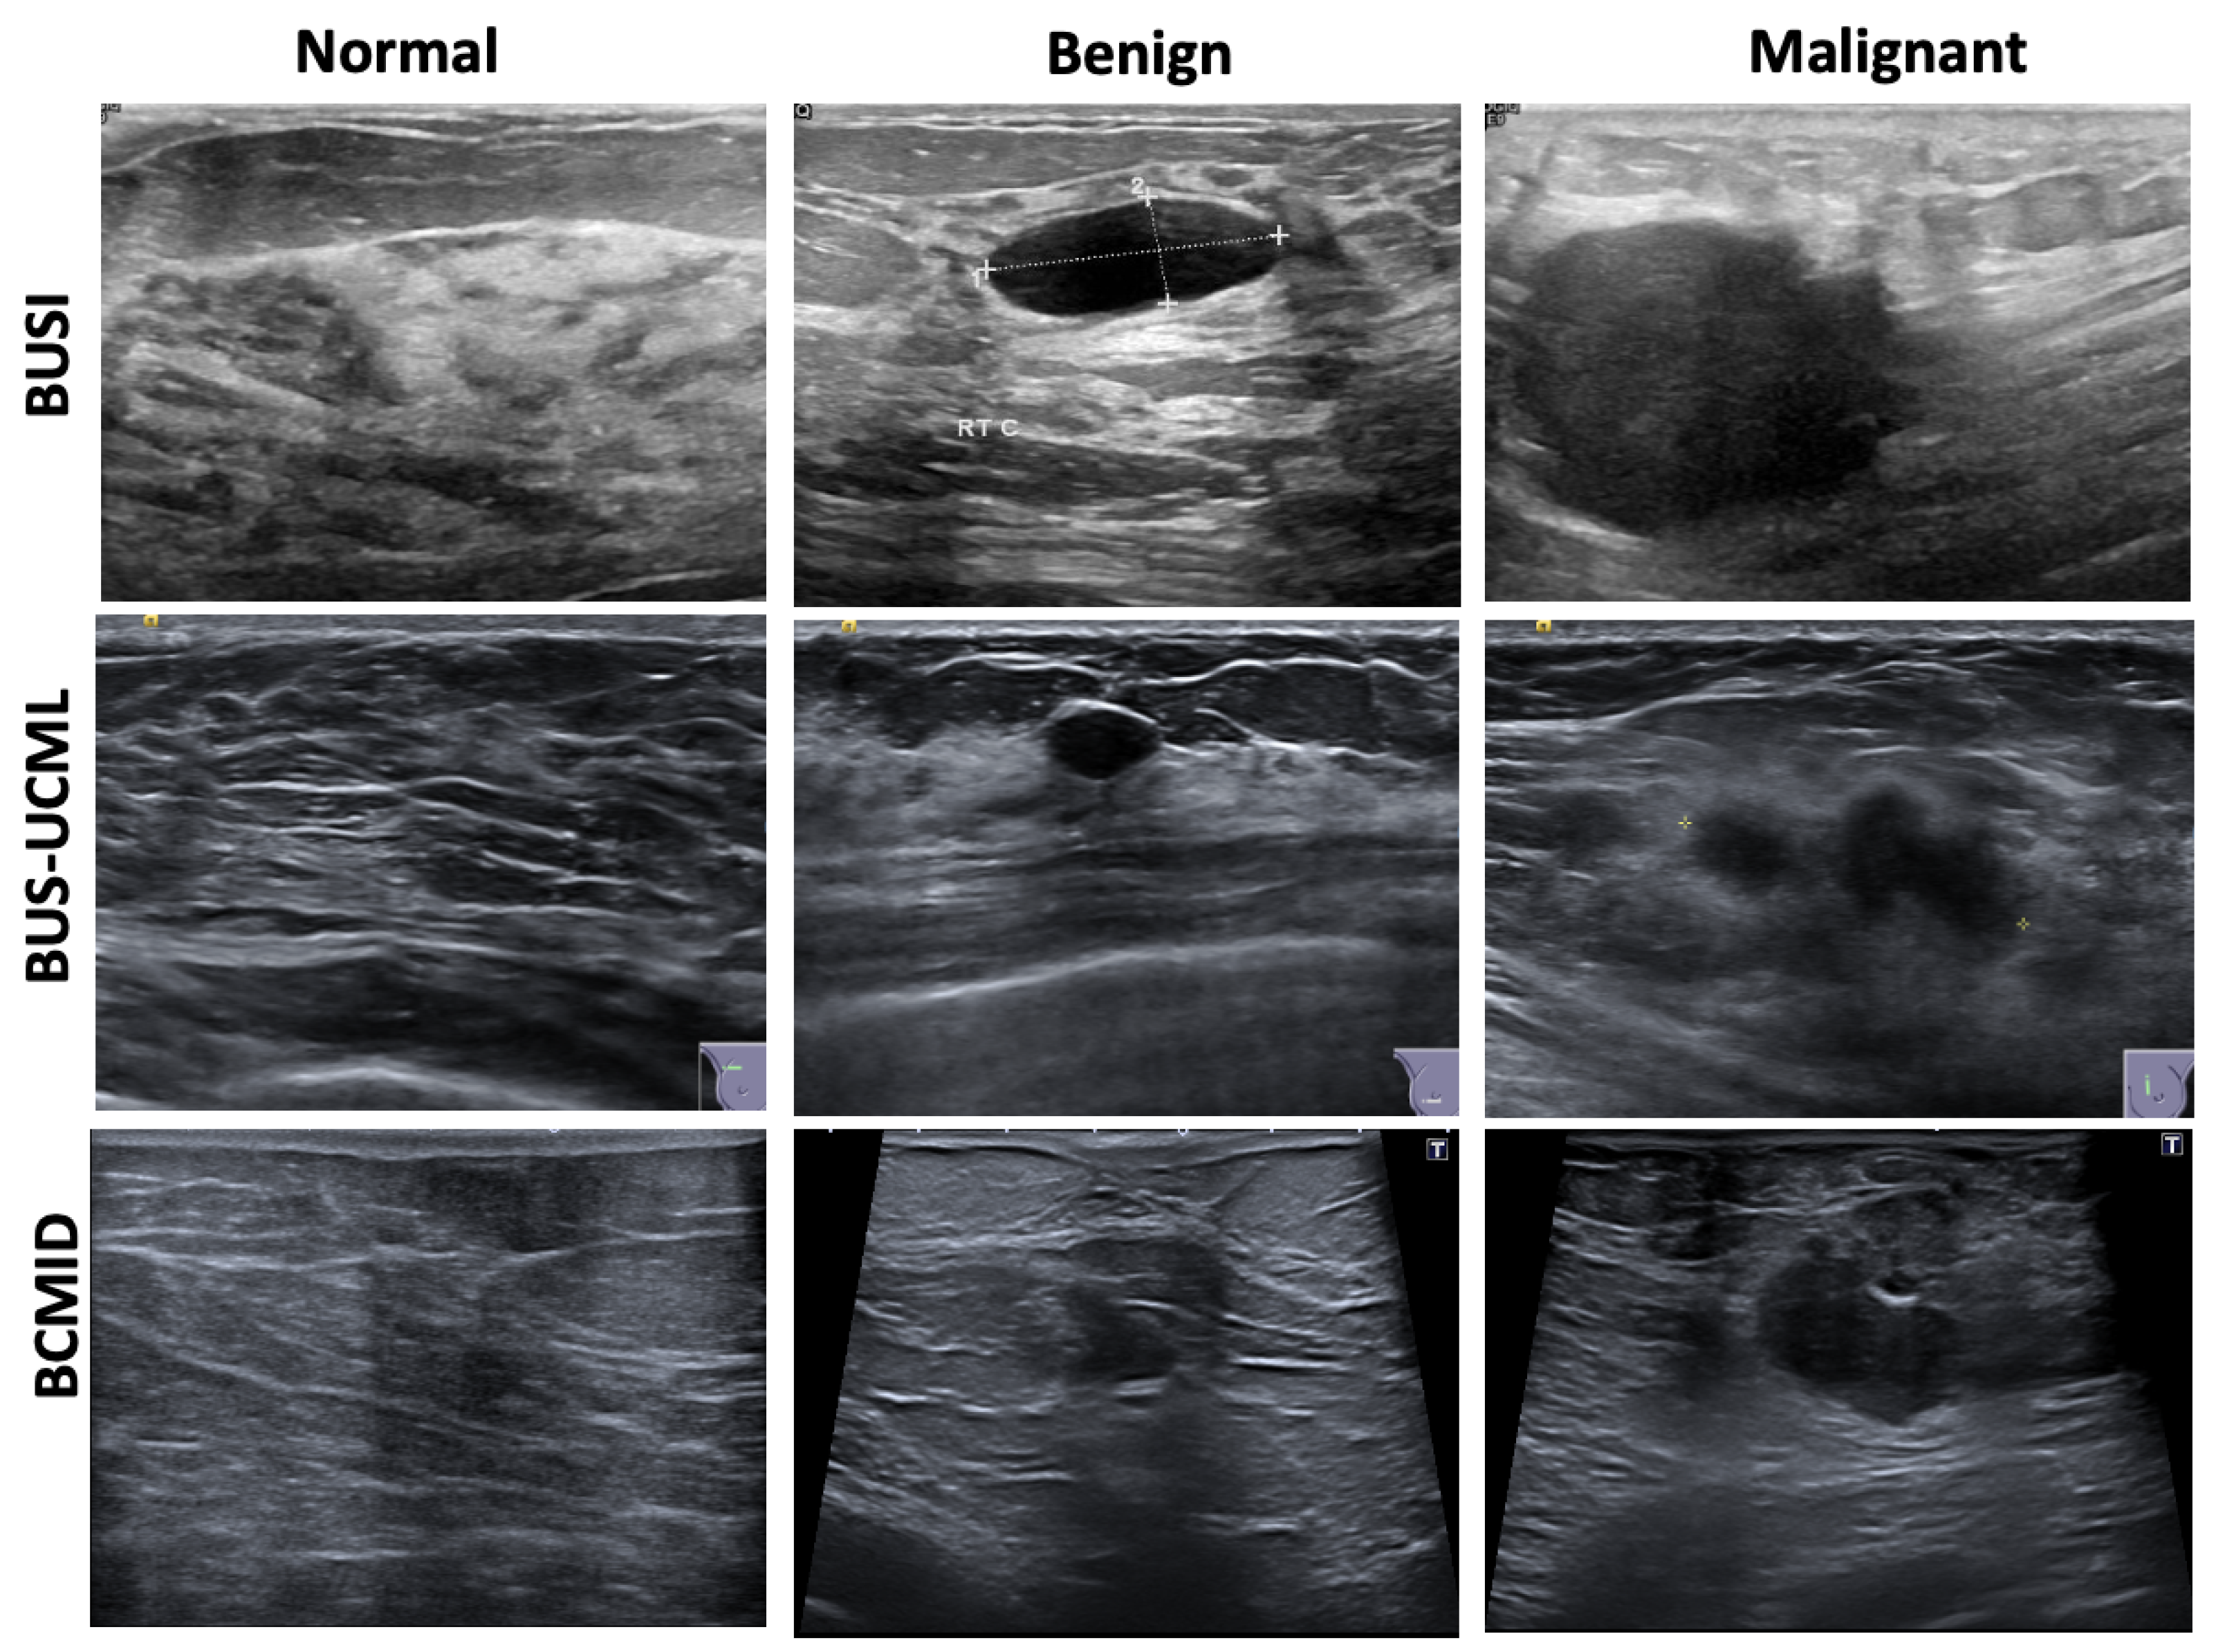

In this section, we provide a detailed description of the three breast ultrasound datasets used to evaluate our model. Moreover, Figure 1 illustrates samples of normal, benign, and malignant cases from each dataset.

3.1.1. BUSI: Breast Ultrasound Images Dataset

The Breast Ultrasound Images Dataset (BUSI) [31] is a collection of annotated ultrasound images collected in 2018 gathered from 600 female patients, with a total of 780 ultrasound images. The images are categorized into three classes: normal, benign and malignant, with 133 normal images, 437 benign images and 210 malignant images. These images are sourced from patients with various breast diseases, ensuring a diverse representation of real-world situations. Every image is carefully annotated by professional physicians, with labels that specify the lesion type and its features. BUSI attempts to improve the precision of automated diagnostic instruments and assist physicians in analyzing ultrasound images.

3.1.2. BUS-UCML: Breast Ultrasound Lesion Segmentation Dataset

The BUS-UCLM (Breast Ultrasound Lesion Segmentation) dataset [32] consists of 681 images obtained from 38 patients gathered between 2022 and 2023 using a Siemens ACUSON S2000 Ultrasound System. It is categorized into three distinct types based on the results: Normal (419 samples), Benign (174 samples), and Malignant (90 samples). Each image comes with a ground truth mask that indicates normal breast tissue (black label), benign tissue (green label), and malignant lesions (red label). This diverse collection of ultrasound images depicting various breast lesions makes the dataset a valuable resource for training and evaluating segmentation algorithms.

3.1.3. BCMID: Breast Cancer Multimodal Imaging Dataset

The Breast Cancer Multimodal Imaging Dataset (BCMID) [33] was collected from 323 adult female patients between 2019 and 2022, with ages ranging from 26 to 82 years at the time of evaluation with total of 1145 imagesw. The dataset was acquired from Ayadi Hospital in Alexandria, Egypt. Data for each patient include ultrasound and mammography scans, along with a validated report that summarizes the physician’s diagnostic conclusion based on the BI-RADS score. Our model incorporated only ultrasound scans. The dataset consists of three classifications: normal, benign, and malignant, with 152 images in the normal class, 734 images in the benign class, and 259 images in the malignant class. The total number of ultrasound images exceeds the number of patients, as each patient may have multiple ultrasound views and/or scans acquired on different dates.